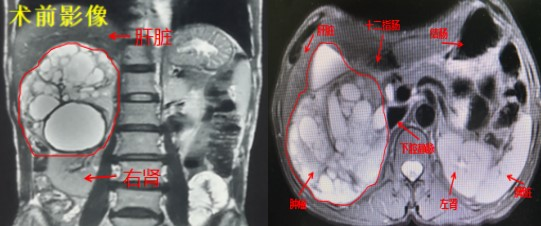

患者罗某,女,56岁,经检查发现巨大肾上腺肿物,且儿茶酚胺中肾上腺素升高,达到基础值的3倍,慕名找到我院泌尿外科负责人徐志强就诊。根据病史、影像资料,化验指标等诊断为右侧肾上腺巨大嗜铬细胞瘤。

嗜铬细胞瘤是一种以分泌儿茶酚胺为主的肾上腺肿瘤,可导致血压的剧烈波动,引起多个器官功能及代谢紊乱,尽早的手术切除是挽救生命健康的最佳治疗手段。但肿瘤血运丰富,且术中不可避免的对肿瘤的挤压,都极易引起血压剧烈波动甚至大出血。

考虑到手术的难度与风险,徐志强组织了多学科会诊(MDT),邀请到我院肝胆外科祁向军主任,仔细研究了手术可行性及具体手术方案。经过周密的论证,制定了完善的手术预案,在与患者及家属进行了充分沟通后,徐志强与科室主任医师王正平于3月16日为患者进行了巨大嗜铬细胞瘤切除术,手麻科副主任医师高波进行手术麻醉。术中专家们逐一攻克了肿瘤血供丰富且与周围脏器粘连严重、血压波动大等难题,最终完整切除肿瘤。患者术后恢复良好,现已康复出院。